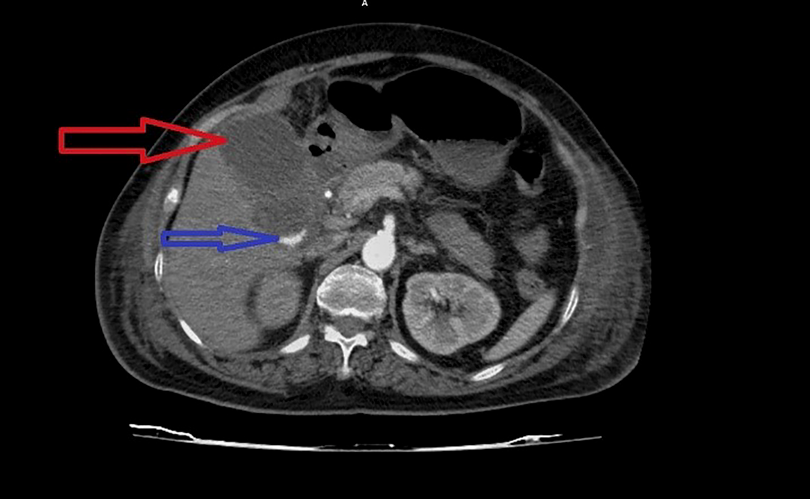

Phim chụp vị trí sỏi túi mật của một trường hợp bệnh điển hình (ảnh BVBM)